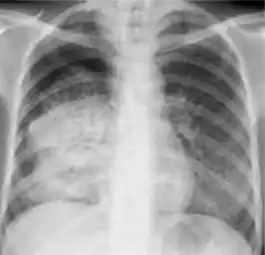

Chest x-ray showing patchy opacification on the upper right and mid-zone lung with fibrotic shadows, as well as bilateral hilar lymphadenopathy.